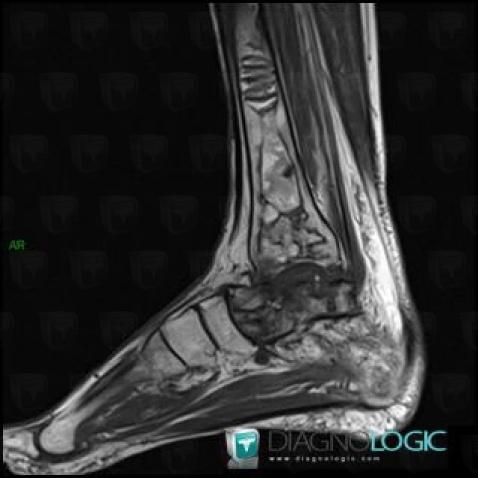

Avascular necrosis, Talus, MRI

Here is the specific information in the key image above:

- Diagnosis Avascular necrosis, Location(s) Talus, with gamuts T2 WI Hypointense bone lesion

Avascular necrosis, Tibia - Distal part, MRI

- Diagnosis Avascular necrosis, Location(s) Tibia - Distal part, with gamuts Well-defined osteolysis, Epiphyseal osteolysis

- Diagnosis Gaucher disease, Location(s) Tibia - Distal part, with gamuts Mulltiple osteolysis